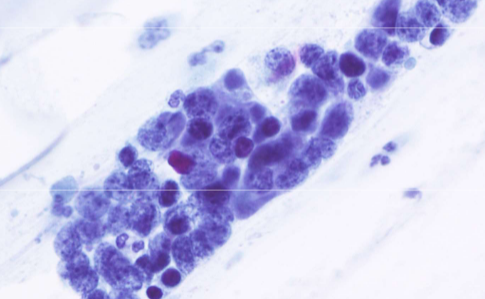

adenocarcinoma